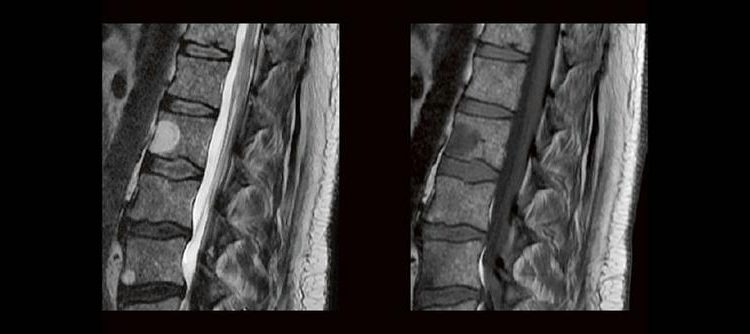

Dorina Petersen In der täglichen Routine hat man wenig Zeit, sich lange mit den Bildern zu beschäftigen, die man anfertigt. Dennoch soll man auf bestimmte Erkrankungen richtig reagieren und die Protokolle anpassen. MTR´s sind keine Ärzte, dennoch gibt es ein Krankheiten, die eindeutige Bildmerkmale zeigen. In diesem Webinar werden eine Reihe solche Erkrankungen gezeigt. Woran […]